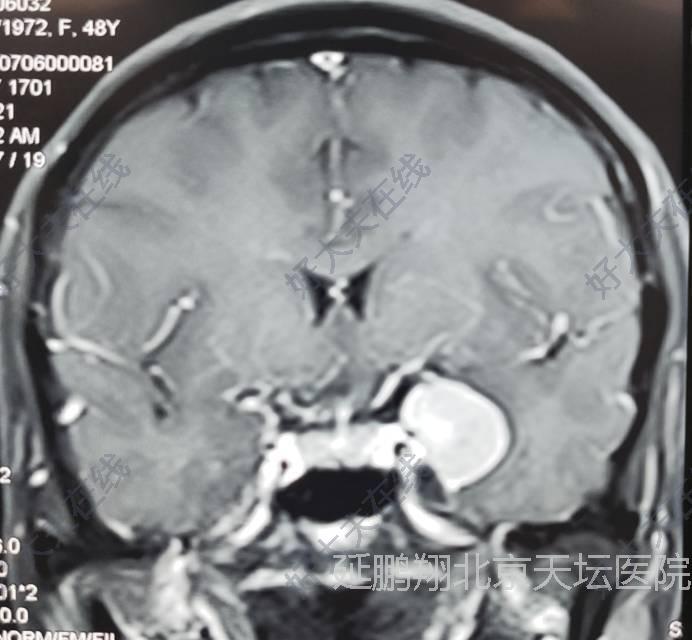

治疗后

术后病人恢复顺利,睡眠,进食,精神状态,行走均正常。常规复查核磁,显示肿瘤消失。